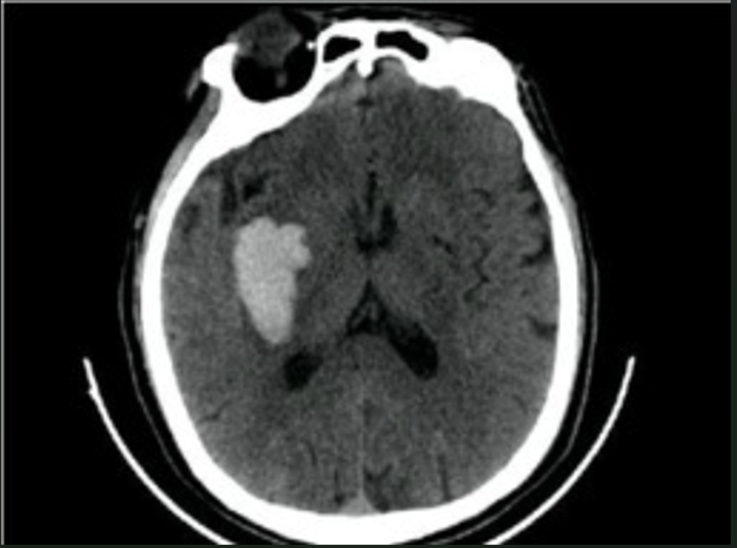

对于上一篇文献而言,在对其进行详细的图像处理后仍未能获得满意的效果。经过反思后发现,在上篇文章中所处理的CT图像中的血块与脑组织的像素范围存在重叠现象。于是我们转而选择了一副全新的CT图像作为样本展开操作,并最终获得了理想的实验结果。

利用聚类算法处理后生成三个预期划分的区域,在这些区域中分离出的血块具有良好的聚类效果,并与周围脑组织区域几乎没有像素值范围上的交集。这种结构特征使得通过阈值分割能够有效地去除黑色脑组织以及其他环状结构。

经分析可得,在此过程中已经较为准确地分离出血块组织;然而,在此过程中仍存在一些零散的像素干扰。为此建议将这些干扰点标记为噪声并予以去除